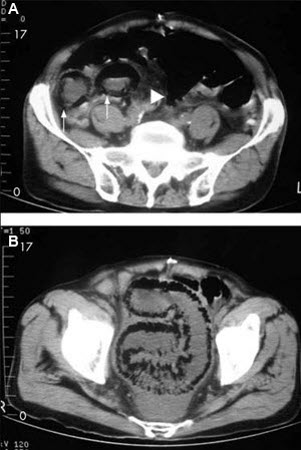

Doença intestinal isquêmica: homem de 84 anos que apresenta sintomas sugestivos de doença intestinal isquêmica: (A) tomografia computadorizada (TC) abdominal que revela uma formação de ar circunferencial maciça e em forma de bastonetes como pneumatose intestinal (setas) e edema pronunciado da gordura mesentérica (ponta de seta) ao redor das alças intestinais necrosadas; (B) outro corte da TC abdominal mostra pneumatose segmentar longa do intestino delgado

Lin I, Chang W, Shih S, et al. Bedside echogram in ischaemic bowel. BMJ Case Reports. 2009:bcr.2007.053462